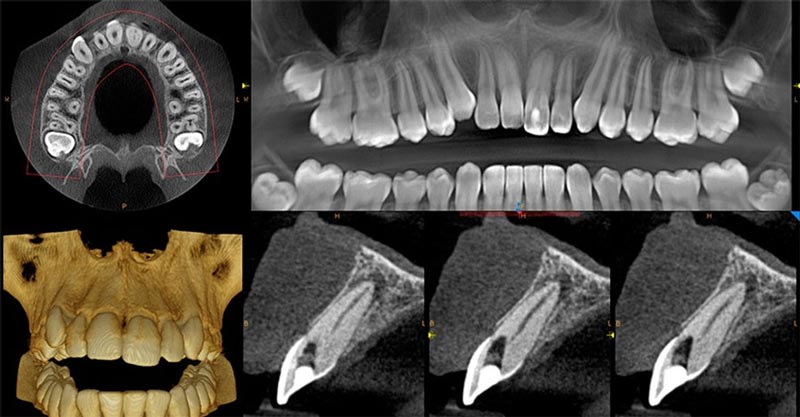

Cone beam computed tomography (CBCT) is an imaging technique that makes use of a rotating X-ray tube device. Similar to a CT scanner. However, the machine can produce very detailed images of that region of the mouth and jaw.

This scan gives a view of the teeth, jawbone, and adjacent structures inside the oral cavity where patients are being scanned. In addition, it allows dentists to evaluate not only the height and orientation of teeth but also the bones with high precision.

- Higher accuracy:While traditional 2D X-ray images show only a limited side and portion of the tooth, CBCT scans 3D imaging offers dentists a complete view of the mouth and jaw to accurately detect surrounding conditions.

- Better treatment planning:CBCT scans provide 3D images that allow accurate and more exact treatment planning, achieving better precision during the surgical procedure.